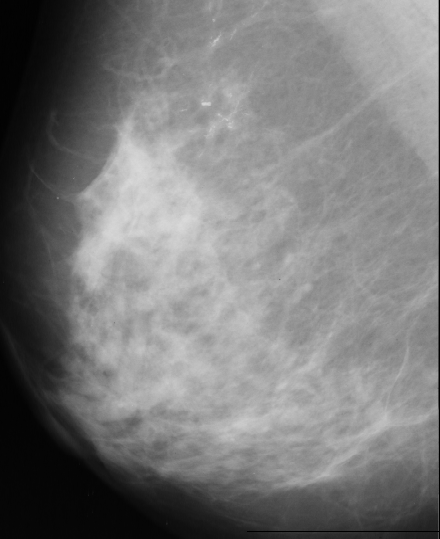

We have used images from http://peipa.essex.ac.uk/ipa/pix/mias/. The images were downloaded from the MIAS MiniMammographic Database, that were digitized at 200µm (the original MIAS Database is digitised at 50µm), with every image being 1024 pixels x 1024 pixels. Tipical mammograms used for image processing are digitized at 35µm-70µm and 4096 gray levels (12 bits), while we worked with mammograms digitized at 200µm with 256 gray levels (8 bits) because of disk space. The use of these low-resolution images caused the disappearance of some microcalcifications that were present in the original images (digitized at 50µm).